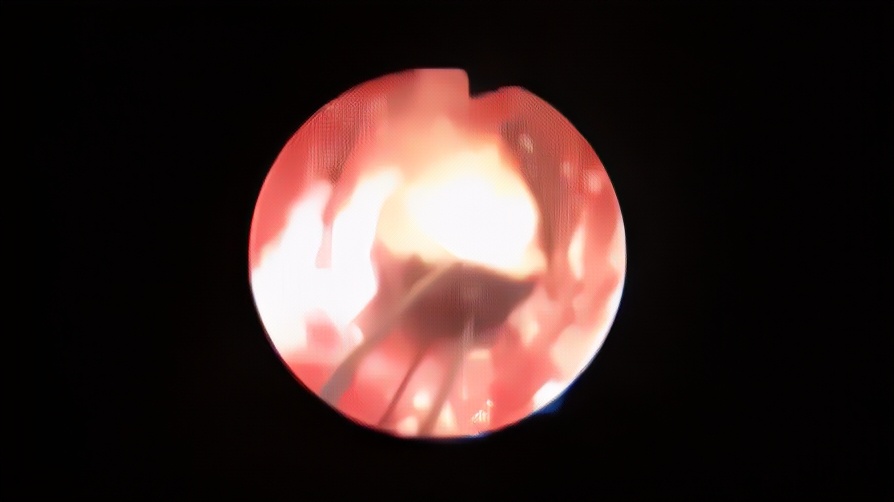

但也有慢性精囊炎,迁延数月不愈,这就要找泌尿外科或男科医生仔细看一看,一般需要做个精囊镜检查,看精囊里是否有射精管梗阻或精囊结石。

这些结石不取出,可以反复刺激精囊造成发炎、出血。一般做个精囊镜就可以取出这些小结石。